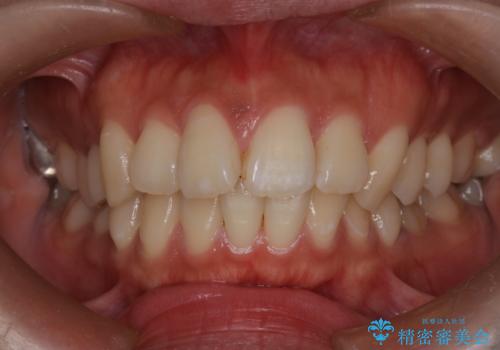

口元の突出感を解消し、横顔を美しく整えるワイヤー矯正

- 口元が出ていること(突出感)を気にされ、これを下げたいという主訴でご来院されました。精密な検査の結果、前歯を大きく後退させ、口元を改善するためには、スペースの確保が不可欠と診断しました。そこで、上下左右の第一小臼歯(4番目の歯)を計4本抜歯し、そのスペースを利用して前歯全体を奥へ移動させる抜歯矯正の治療計画を立案。確実な歯の移動を実現するため、ワイヤー矯正装置を使用しました。

今回の矯正治療では、口元の突出感を解消するためのスペースを確保するため、計画通り上下左右4本の小臼歯を抜歯しました。装置には、確実な歯の移動と細やかな調整が可能なワイヤー矯正を採用。抜歯によってできたスペースを最大限に利用し、前歯を奥へ、そして垂直的に慎重に移動させました。

治療の結果、長年のコンプレックスであった口元の突出感が大幅に解消され、横顔のライン(Eライン)が美しく改善しました。機能的な咬み合わせを確立すると同時に、患者様が望んでいた審美的な口元を獲得していただけました。